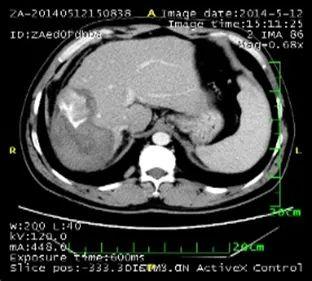

2. 肺部病灶治疗前后核磁对比:

肺部转移病灶在用药后2个月明显缩小,4个月后病灶基本消失。

治疗前

治疗2个月

治疗4个月

治疗6个月

治疗16个月